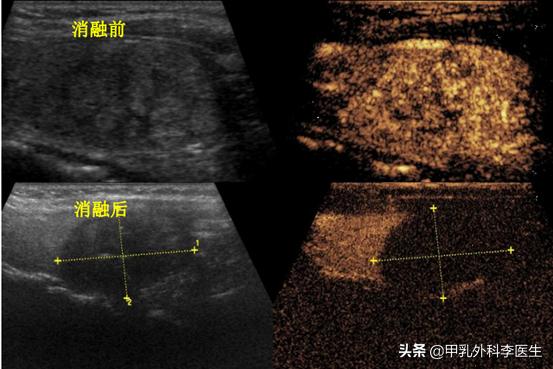

消融前后通过超声造影可以看出消融后肿块完全失活